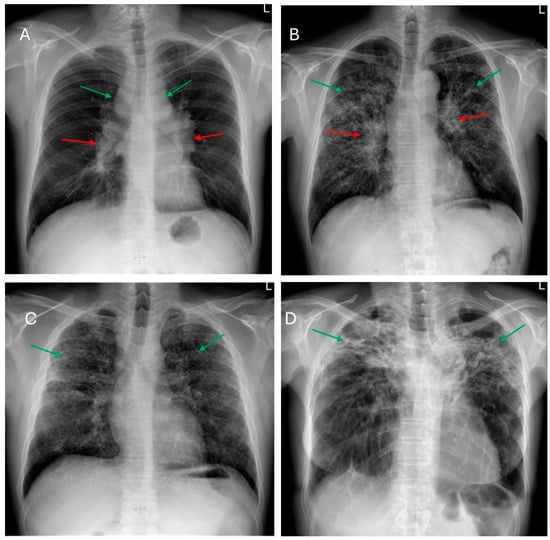

5. Radiological Aspects of Fibrotic Pulmonary Sarcoidosis

5.1. Key HRCT Findings in fPS